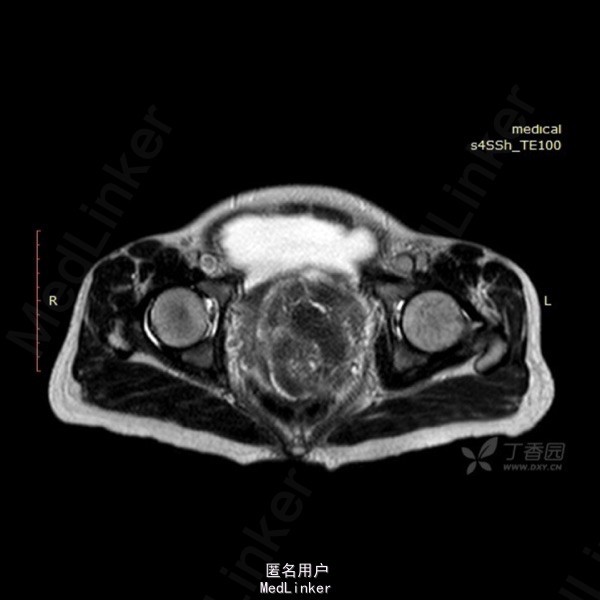

影像表现:左侧附件区示一巨大的病变,呈长T1长T2异常信号影,期内多发分隔,增强后呈不均匀强化,强化较明显。DWI示低信号。总的来看,病变为一个巨大肿块,内有分隔,境界较清。 诊断:我认为首选左侧阔韧带子宫肌瘤可能性大。由于其短期内增大,不除外瘤内出血的可能。 转于:丁香园